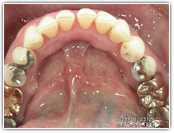

メタルフリーへの取り組み

当院では、金属の詰め物が平均7年でやり替えられている事実、そして金属アレルギーの誘発や歯茎の黒ずみといった肉体に与えるデメリットを避けるためにも金属を使わない「メタルフリー」の治療を推奨しています。

あなたは なぜか歯医者さんで治した歯だけがまた悪くなると感じたことはありませんか。そしてそれは銀歯ではありませんか。残念なことに、保険でつめた銀歯(金銀パラジウム合金)は5~7年でやり替えられているという統計が出ています。